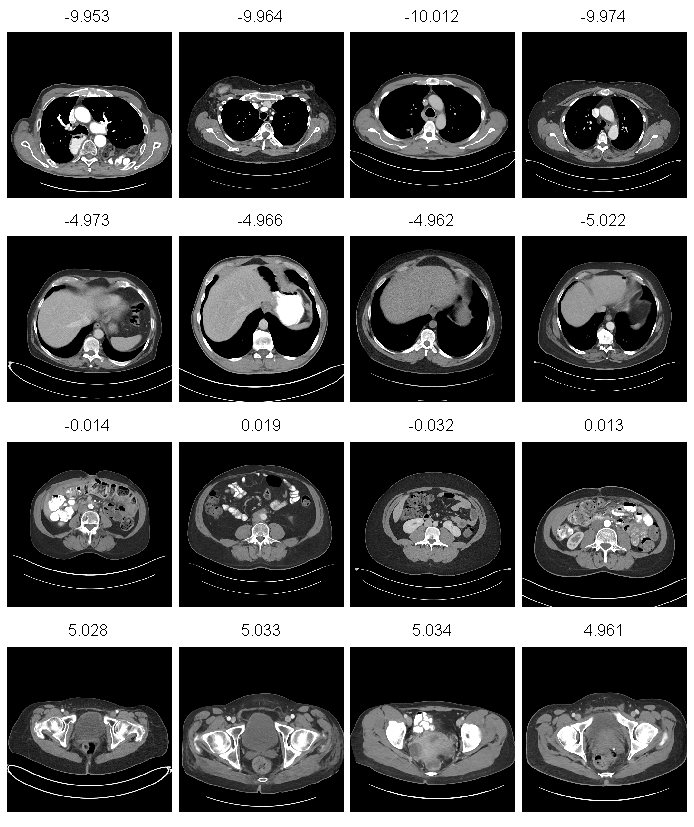

Under our defined loss function (Eq. 3), the UBR output scores mostly range between -15 and 15. Fig. 2 illustrates some qualitative results. It can be observed that the deeply learned regression scores and human anatomical body parts correspond well (-10: upper chest, -5: liver dome, 0: lower abdomen, 5: lower pelvis). UBR is also robust to the varying position, size and pathological conditions (e.g., row 1 column 1, atypical presentation of bowel in the chest) of the human body.